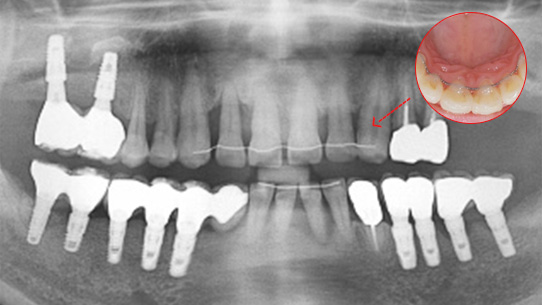

심한 염증과 기존 보철물의 오염상태가 심해 다른 병원에서 임플란트 17개 진단을 받고 내원, 특히 앞니부분의 치조골이 많이 약해져 흔들림이 심하여 바로

치주치료를 시행하였습니다. 치주치료 2주 후 앞니 잇몸이 개선되어 발치 하지 않고 교정 유지장치를 이용하여 흔들림을 보완하였습니다.

오염된 보철물을 제거하고 임플란트 11개를 식립하였습니다.

심한 염증으로 치아가 흔들리는 상태

앞니 흔들림을 보완하는 유지장치 부착